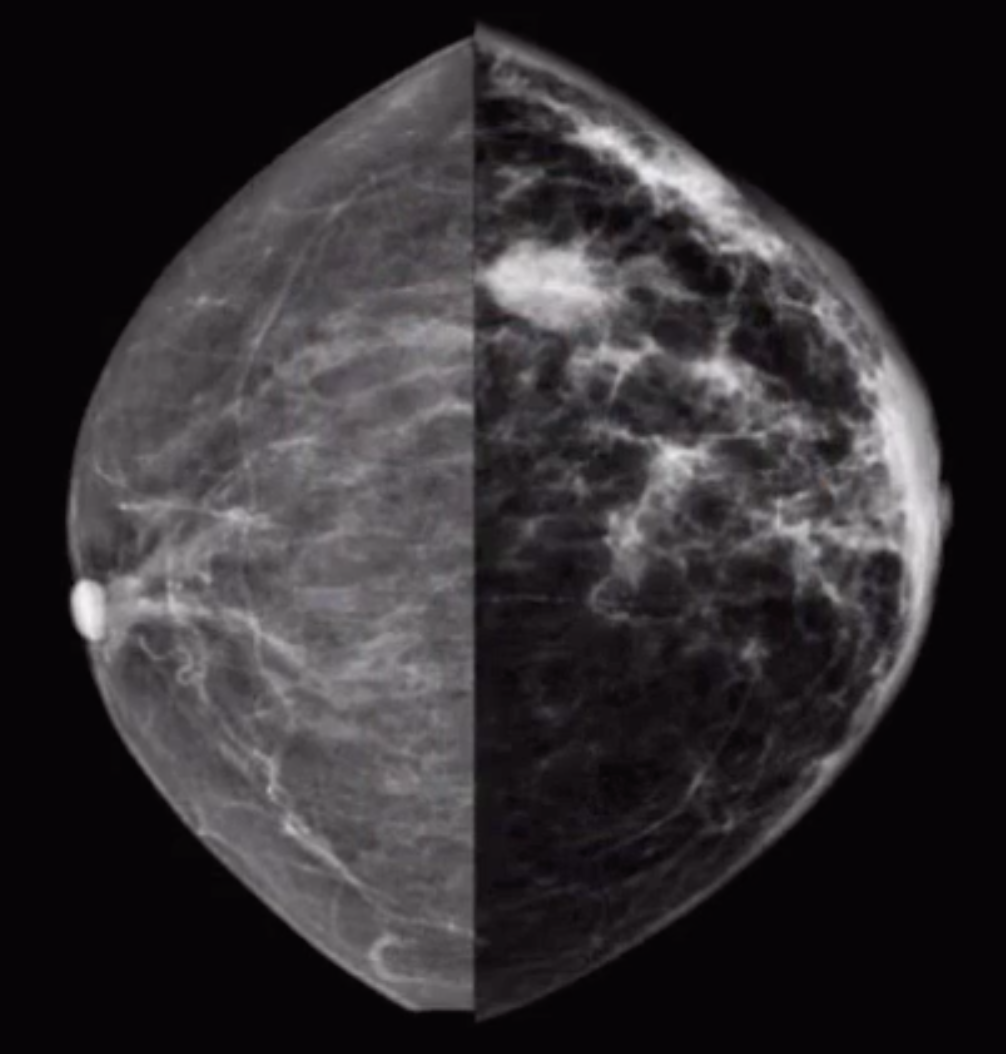

• Architectural distortion without definitive central mass on MG

• Shadowing on US without evidence of definitive mass

Dark Star DDx

• Architectural distortion without definitive mass

• Invasive lobular carcinoma

• Radial scar

• Postsurgical scarring

• IDC-NOS subtype